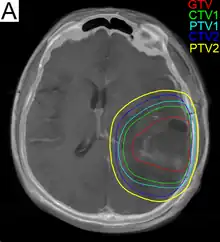

.png)

Subsequent to surgery, radiotherapy becomes the mainstay of treatment for people with glioblastoma. It is typically performed along with giving temozolomide.[10] A pivotal clinical trial carried out in the early 1970s showed that among 303 GBM patients randomized to radiation or best medical therapy, those who received radiation had a median survival more than double those who did not.[79] Subsequent clinical research has attempted to build on the backbone of surgery followed by radiation. Whole-brain radiotherapy does not improve when compared to the more precise and targeted three-dimensional conformal radiotherapy.[80] A total radiation dose of 60–65 Gy has been found to be optimal for treatment.[81]

GBM tumors are well known to contain zones of tissue exhibiting hypoxia, which are highly resistant to radiotherapy. Various approaches to chemotherapy radiosensitizers have been pursued, with limited success as of 2016. As of 2010, newer research approaches included preclinical and clinical investigations into the use of an oxygen diffusion-enhancing compound such as trans sodium crocetinate as radiosensitizers,[82] and as of 2015 a clinical trial was underway.[83] Boron neutron capture therapy has been tested as an alternative treatment for glioblastoma, but is not in common use.